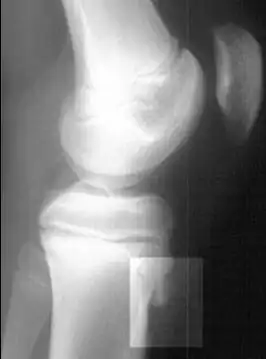

Рентгенограмма коленного сустава в боковой проекции, демонстрирующая фрагментацию большеберцовой бугристости с отёком окружающих мягких тканей. Разрушение костной ткани.

• Рентгенографическое исследование коленных суставов в боковых проекциях; часто наблюдаются характерные «хоботки» в области бугристости большеберцовых костей, нередко вводящие врачей в заблуждение; изолированные костные фрагменты небольших размеров, иногда в количестве 1-2-3. Картина представляется очень разнообразной, напоминающей дробления, искривления и надломы эпифизарного отростка.